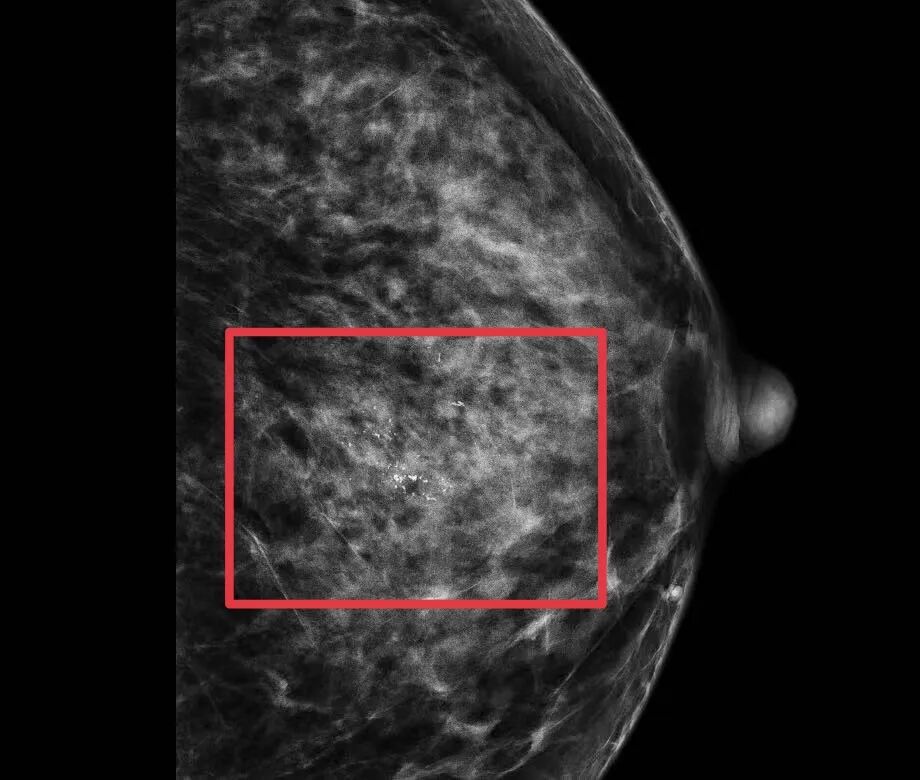

在乳腺癌治疗领域,总有一些病例因其特殊的挑战性而显得尤为珍贵。近日,和祐医院苏逢锡乳腺肿瘤中心团队就遇到了这样一位特殊的患者——穿刺病理诊断为导管原位癌,但术前钼靶检查显示钙化广泛分布,分布于接近半个乳房,保乳困难。按照常规诊疗标准,如此大范围的病灶通常建议行乳房全切术。

经活检明确腋窝淋巴无转移后,团队开始了保乳手术的核心步骤。取左侧乳房外下皱襞弧形切口,精细分离皮下组织,准确定位肿瘤所在。随后,团队沿肿物周围 1.0 厘米安全边界完整切除肿物(切除范围:9*7*2 cm),并同步获取乳头后组织及手术残腔周边多处边缘组织送检。通过术中冰冻病理检查,实时评估切缘是否阴性,为保乳成功奠定了坚实的安全基础。